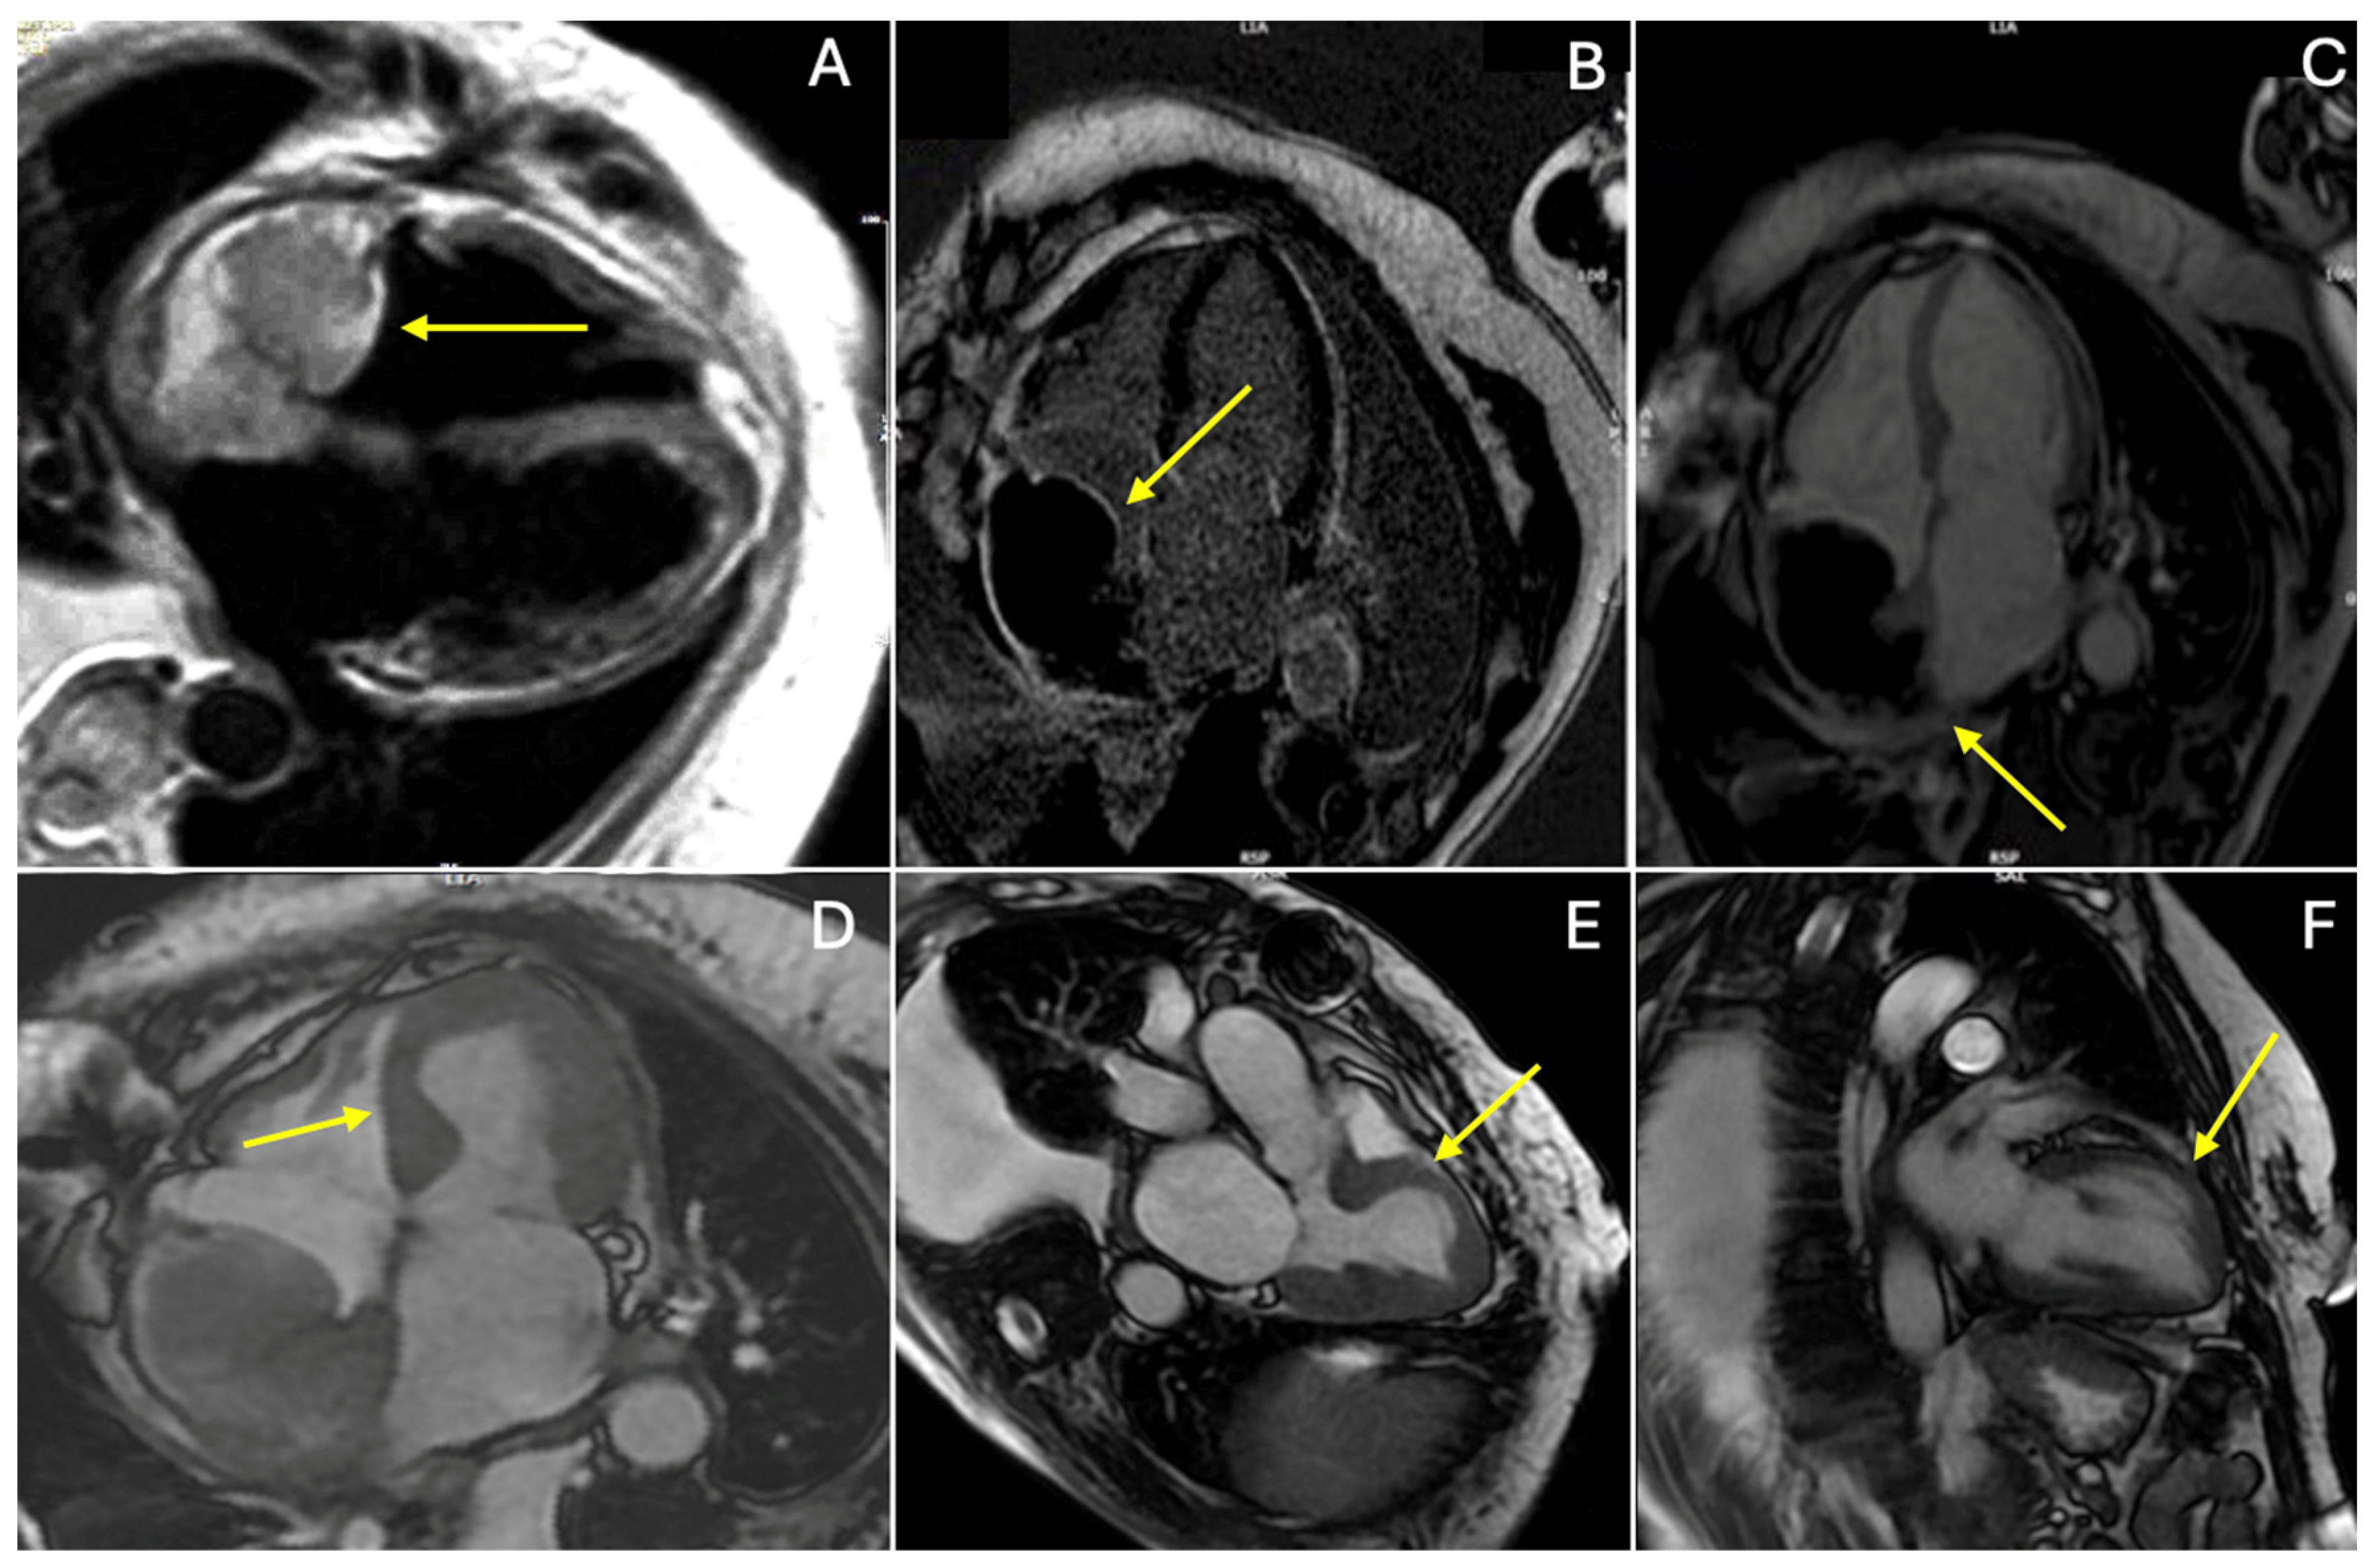

2. Case Presentation